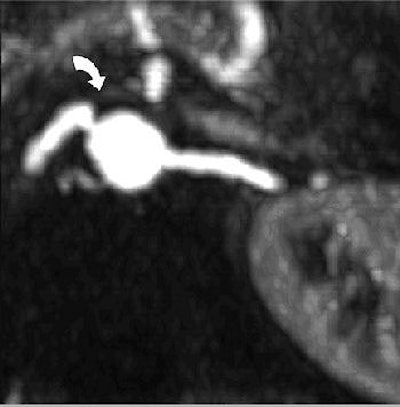

| Twenty-year-old man with large right inferior accessory hepatic vein. Balanced turbo field-echo images (above, axial image; below, coronal image) reveal a 7.3-mm right inferior accessory hepatic vein (arrow) entering inferior vena cava. Lim JS, Kim M, Kim JH, Kim SI, Choi J, Park M, Oh YT, Yoo HS, Lee JT, Kim KW, "Preoperative MRI of Potential Living-Donor-Related Liver Transplantation Using a Single Dose of Gadobenate Dimeglumine" (AJR 2005;185:424-431). |